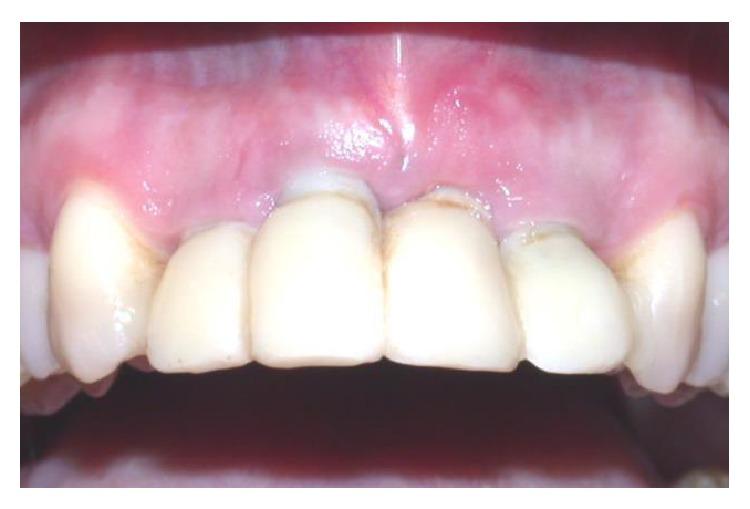

The functional and aesthetic restoration of teeth compromised due to aggressive periodontitis presents numerous challenges for the clinician. Horizontal bone loss and soft tissue destruction resulting from periodontitis can impede implant placement and the regeneration of an aesthetically pleasing gingival smile line, often requiring bone augmentation and mucogingival surgery, respectively. Conservative approaches to the treatment of aggressive periodontitis (i.e., treatments that use minimally invasive tools and techniques) have been purported to yield positive outcomes. Here, we report on the treatment and five-year follow-up of patient suffering from aggressive periodontitis using a minimally invasive surgical technique and implant system. By using the methods described herein, we were able to achieve the immediate aesthetic and functional restoration of the maxillary incisors in a case that would otherwise require bone augmentation and extensive mucogingival surgery. This technique represents a conservative and efficacious alternative to the aesthetic and functional replacement of teeth compromised due to aggressive periodontitis.

侵袭性牙周炎导致牙齿功能和美观受损,给临床医生带来诸多挑战。牙周炎引起的水平骨吸收和软组织破坏会妨碍种植体植入以及美观的牙龈微笑线的再生,通常分别需要进行骨增量和膜龈手术。据称,侵袭性牙周炎的保守治疗方法(即使用微创工具和技术的治疗方法)能产生积极效果。在此,我们报告了一名侵袭性牙周炎患者采用微创外科技术和种植系统的治疗及五年随访情况。通过使用本文所述方法,在原本需要骨增量和广泛膜龈手术的病例中,我们成功实现了上颌切牙的即刻美观和功能恢复。该技术是侵袭性牙周炎导致牙齿功能和美观受损时,一种保守且有效的替代治疗方法。